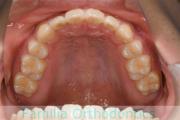

下の前歯が後ろにあるのが気になるとのことで来院されました。非抜歯で行うことも可能でしたが、上下左右から小臼歯抜歯をして治療を行うことをご希望になりました。

マルチブラケット法にて治療を行い、約3年、40回の通院が要でした。

かみ合わせが深い(上の前歯で下の前歯が覆われてしまう)ので、保定をしっかりしないと、また深くなってきてしまいやすいです。